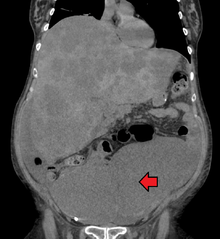

Colorectal cancer diagnosis is performed by sampling of areas of the colon suspicious for possible tumor development, typically during colonoscopy or sigmoidoscopy, depending on the location of the lesion. Disease extent is usually determined by a CT scan of the chest, abdomen and pelvis. Other potential imaging tests such as PET and MRI may be used in certain cases. Colon cancer staging is done next, based on the TNM system which considers how much the initial tumor has spread, if and where lymph nodes are involved and the extent of metastatis.[15]

PET/CT of a staging exam of colon carcinoma. Besides the primary tumor a lot of lesions can be seen. On cursor position: lung nodule.